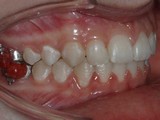

Zkřížený skus, předkus, nedostatek místa pro špičák. Léčba pomocí aparátu Hyrax a dále fixními aparáty v obou čelistech s jumping aparátem. V ústech přítomné MARA-stopy na dočasnou stabilizaci výsledku.

Před léčbou        Po léčbě

pravo pac2       prava pac2